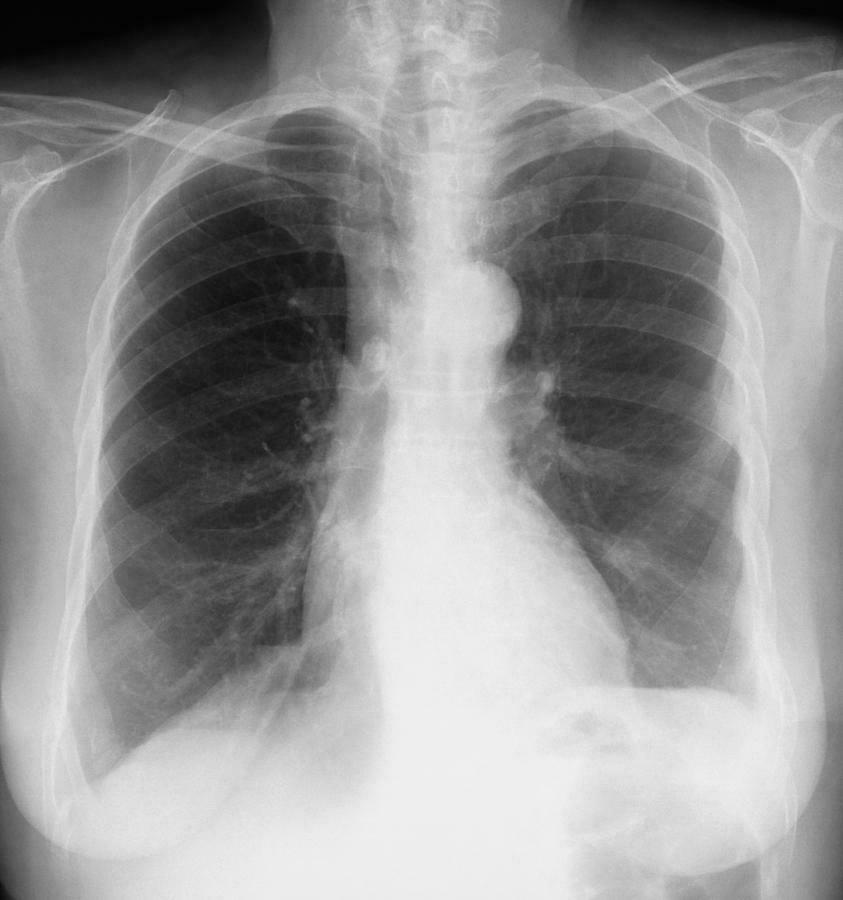

O que é o Sinal da borboleta? Quais são suas características radiológicas? Opacidade alveolar bilateral em campos pulmonares médios. -Diminuição simétrica da transparência pulmonar perto do hilo, poupando periferia -Significa edema alveolar extenso em edema agudo de pulmão/ICC. -Infiltrado que preserva a periferia.